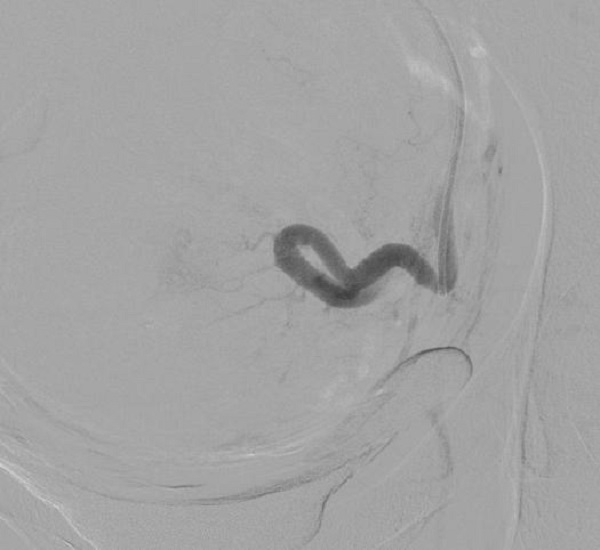

手术从股动脉进行血管穿刺,创伤小,恢复快,完整保留子宫。术中可见子宫肌瘤血供明显。

(栓塞后子宫肌瘤无血运)

术后第二天患者下床活动自如,穿刺伤口已完全恢复。经过短暂药物辅助治疗后,子宫肌瘤触诊较前明显减小,无腹痛、腹胀,尿频、肛门坠胀感均较前明显好转。患者十分满意,目前已康复出院。